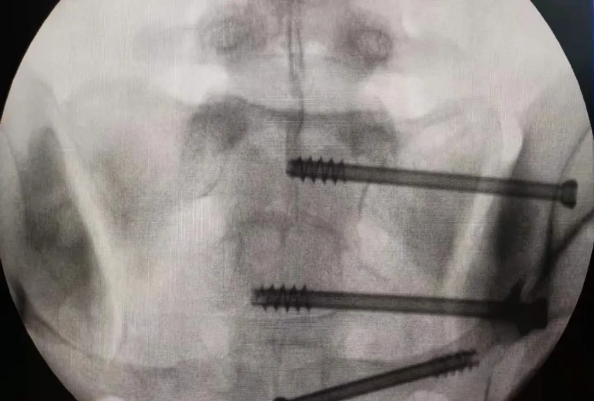

在南昌市第一醫(yī)院廖琦教授帶領(lǐng)下,由創(chuàng)傷骨科團(tuán)隊(duì)借助天璣?骨科手術(shù)機(jī)器人為患者“量身定做”最理想、最安全的教科書般的通道,完美安全微創(chuàng)完成手術(shù),并且手術(shù)時(shí)間明顯縮短,真正做到“指哪兒打哪兒”!更讓患者放心的是,天璣?骨科手術(shù)機(jī)器人的“穩(wěn)定手”機(jī)械臂進(jìn)行精準(zhǔn)定位,不用反復(fù)探尋。